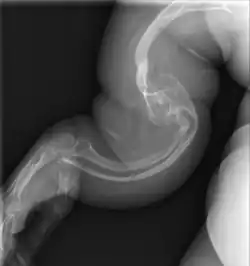

![]() несовершенный остеогенез V типа у взрослого | |

Несоверше́нный остеогене́з (НО) (лат. osteogenesis imperfecta; иначе «несовершенное костеобразование», болезнь «хрустального человека», болезнь Лобштейна — Вролика) — группа генетических нарушений. Одно из заболеваний, характеризующееся повышенной ломкостью костей. Больные либо имеют недостаточное количество коллагена, либо его качество не соответствует норме. Так как коллаген — важный белок в структуре кости, это заболевание влечёт за собой слабые или ломкие кости.

Существуют основные четыре типа НО. I тип наиболее частая и лёгкая форма, за которой следуют II, III и IV типы. Сравнительно недавно были классифицированы типы V, VI, VII и VIII которые разделяют те же клинические особенности что и 4-й, но каждый из них имеет уникальные гистологические и генетические данные.